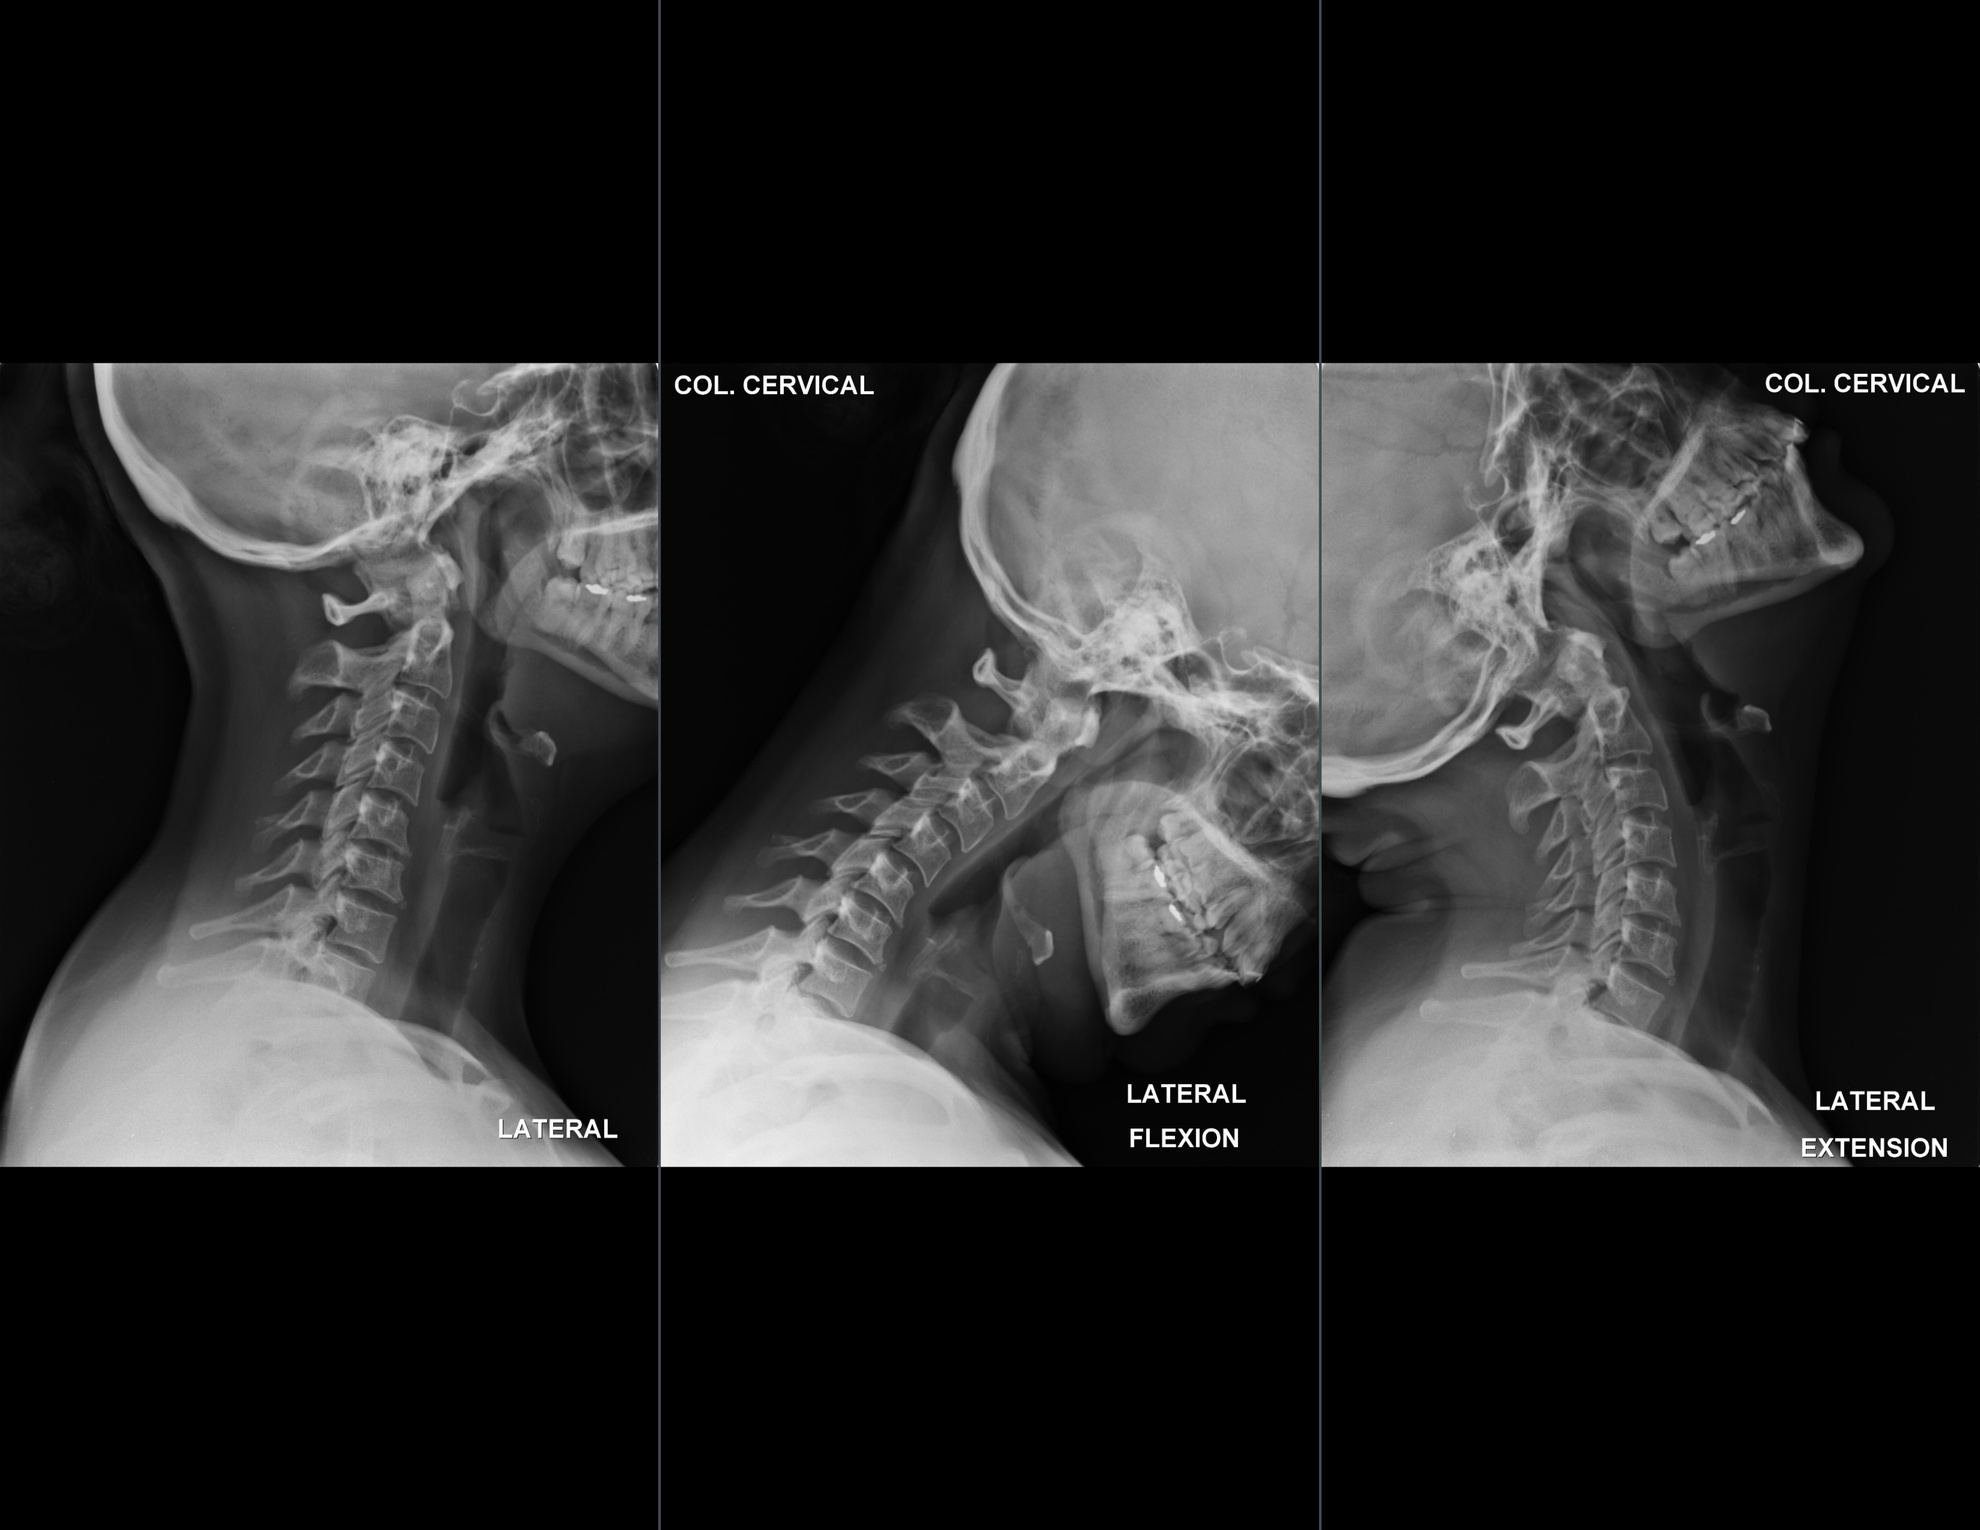

En centro de Imagen Radium ofrecemos estudios de Radiología e Imagen Médica de alta precisión a un precio justo, con equipos de última generación.

Imágenes de Alta Precisión.